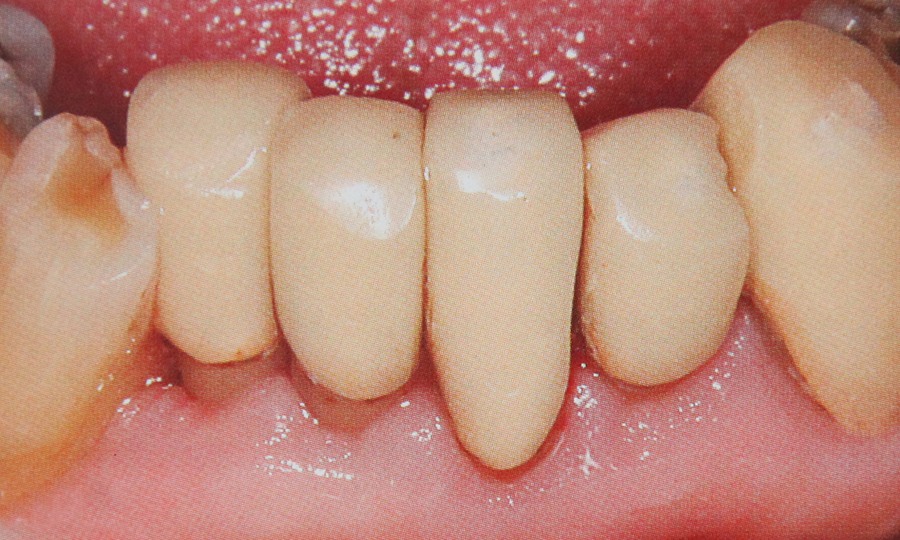

Parodontologie

Ca stiinta de baza a stomatologiei a cunoscut remarcabile progrese in domeniul etiopatogeniei profilaxiei si tratamentului. Considerata multa vreme ca o boala cu evolutie incerta si un prognostic incert, boala parodontala poate fi astazi controlata prin proceduri terapeutice complexe si eficiente in care rolul tratamentului antimicrobian este predominant. Boala parodontala e necesar sa fie privita ca un proces patologic complex care trebuie abordat numai printr-un “pachet” de masuri terapeutice medicamentoase, chirurgicale locale si generale.

Afectinile gingivale sunt cea mai importanta cauza a pierderii dintilor la populatia adulta. Cu o ingrijire adecvata, periaj regulat, folosirea atei dentare, vizite periodice pentru detartraj si periaj profesional pot ajuta la evitarea bolilor parodontale. Bolile parodontale sunt cauzate de bacterii sub forma de placa microbiana sau tartru. Cu totate ca placa microbiana este principala cauza a bolii exista si alti factori care o favorizeaza ca: fumatul, utilizarea contraceptivelor, punti neadaptate, obturatii dentare vechi, anumite boli sistemice, anumite tipuri de steroizi sau alte medicamente. In stadii  incipiente afectiunea poarta numele de gingivita si poate fi prevenita tratata si vindecata. Netratata insa poata duce la boli dentare care afecteaza tesutul gingival si in final duce la pierderea dintilor